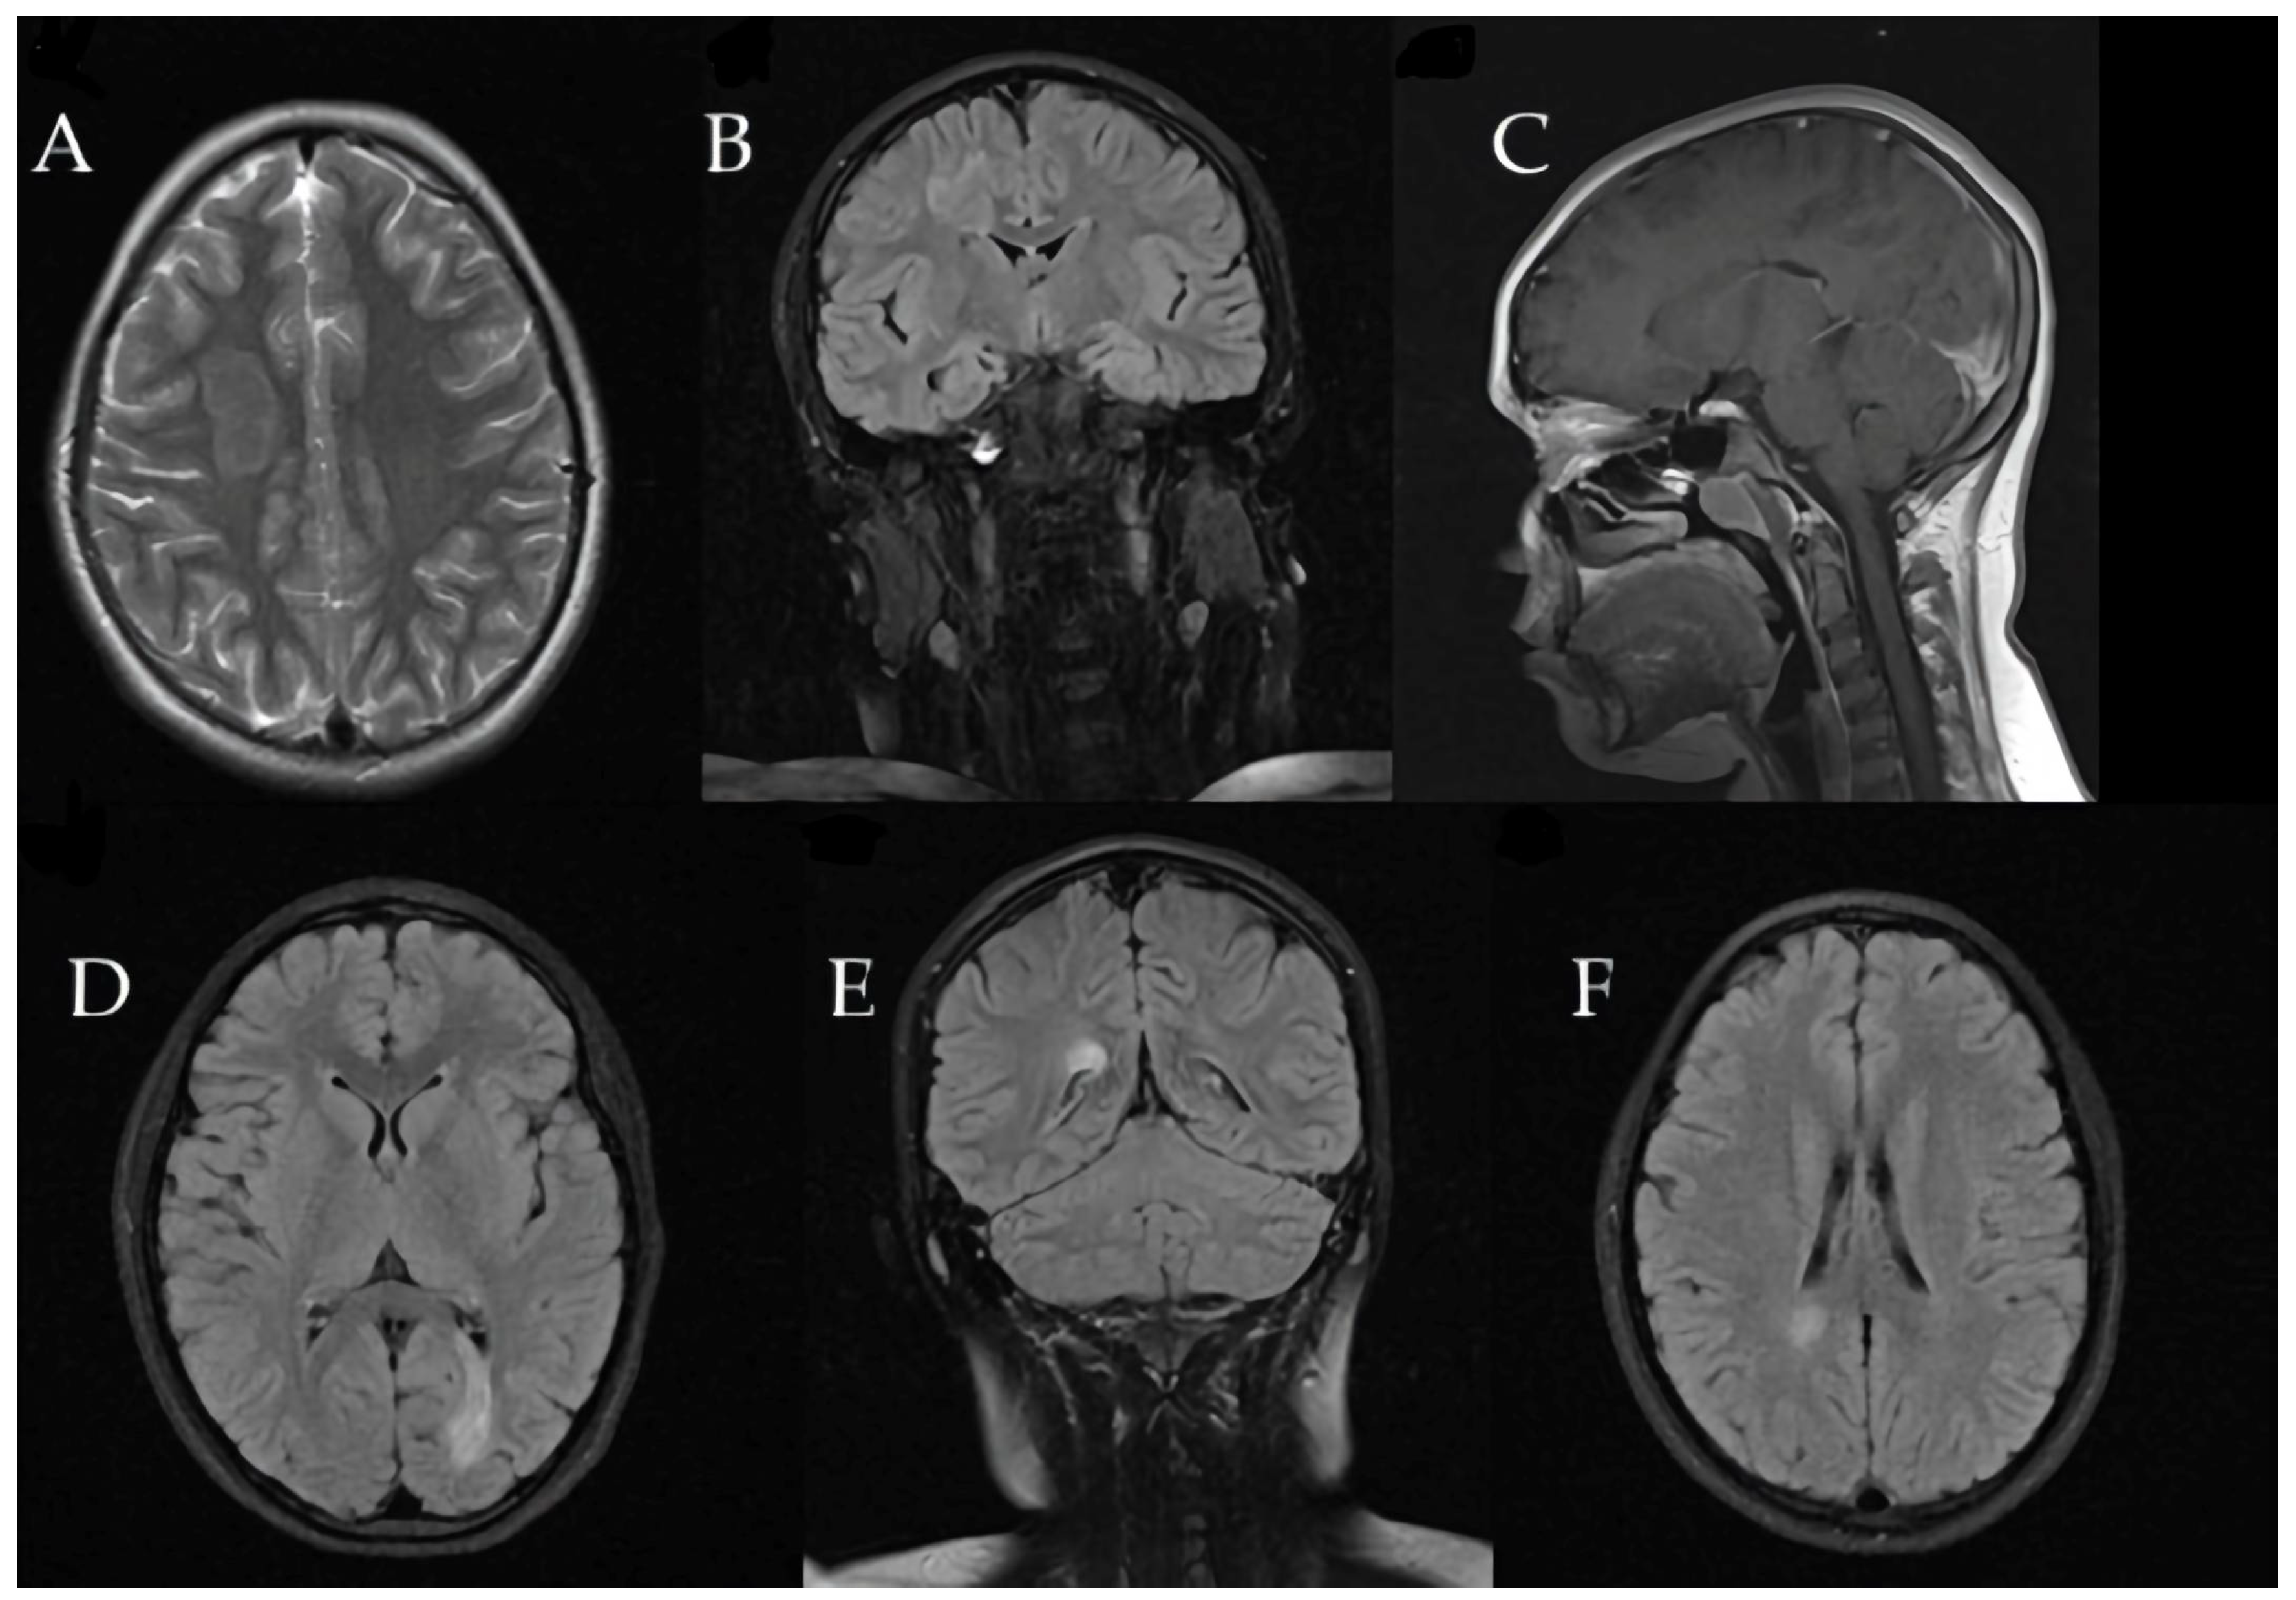

Brain MRI revealed a large tumefactive demyelinating lesion in the right frontal lobe (centrum semiovale region). Additionally, multiple smaller hyperintense lesions were observed in the white matter on T2/FLAIR images, raising a broad differential diagnosis that included inflammatory demyelination (atypical MS), CNS infection, or a vascular event (ischemia).

These initial imaging findings are shown in Figure 4.

Figure 4. (AF) First MRI shows right F-centrum semiovale lesion (A) Axial T2-weighted image reveals moderate peripheral vasogenic edema. (B,DF) Coronal and axial FLAIR sequences clearly illustrate the hyperintense appearance of the lesion, perifocal edema, and bilateral demyelinating lesions. (C) Sagittal T1-weighted post-contrast sequence highlights late peripheral enhancement measuring 24 × 15.5 × 20.4 mm and lesion localization.